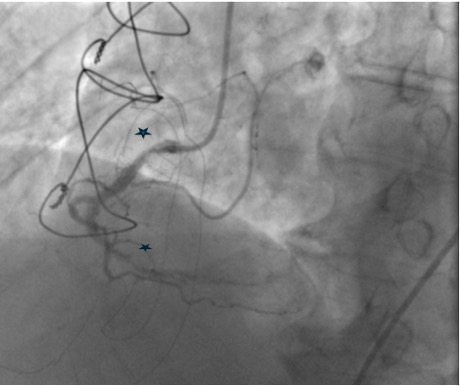

Coronary angiogram showed patent LIMA to LAD graft mild proximal circumflex disease. The right coronary artery showed proximal 60% calcific stenosis and distal RCA 99% focal calcific lesion with TIMI II distal flow. PCI was attempted but failed due to wire uncrossability of the distal lesion and the inability to deliver devices beyond the proximal lesion. As he had recurrent ACS, he was admitted for PCI of RCA

Right femoral arterial access was taken with 7F long sheath (45cm) and RCA was engaged with 7F AL 3.5 catheter. We failed to cross proximal lesion with Rinato wire (Asahi Intecc, Japan) but crossed with Fielder XT-R (Asahi Intecc, Japan). We had difficulty in crossing the distal lesion due to inadequate guide support and inability to deliver microcatheter beyond proximal calcific lesion. Proximal lesion was predilated with 2.5 mm NC balloon but the balloon got ruptured. Fielder XTR wire was exchanged with Rota floppy wire (Boston scientific, Japan) with corsair microcatheter (Asahi Intecc, Japan) delivered just beyond proximal lesion. Temporary pacemaker inserted and Rotablation of the proximal RCA lesion was done with 1.5 mm Rota burr. Post proximal lesion modification corsair could be delivered to Distal lesion, and lesion crossed with Ultimate Bros 3 (Asahi Intecc, Japan) followed by de-escalation to Fielder XT-R wire. The proximal lesion was then dilated with 3.5x10mm Wolverine Cutting balloon (Boston Scientific, Ireland) to deliver a 7F Guideliner beyond the proximal lesion for better support to further gear advancement. As 1mm balloon stuck within the distal lesion, grenadoplasty was performed followed by an exchange to rota wire with corsair. Rotablation of distal RCA lesion was done with 1.5 mm burr through guide extension. Further dilatation of distal lesion was done with 3mm IVL balloon followed by stenting with 3.25 x 28 mm drug-eluting stent with good TIMI 111 flow.